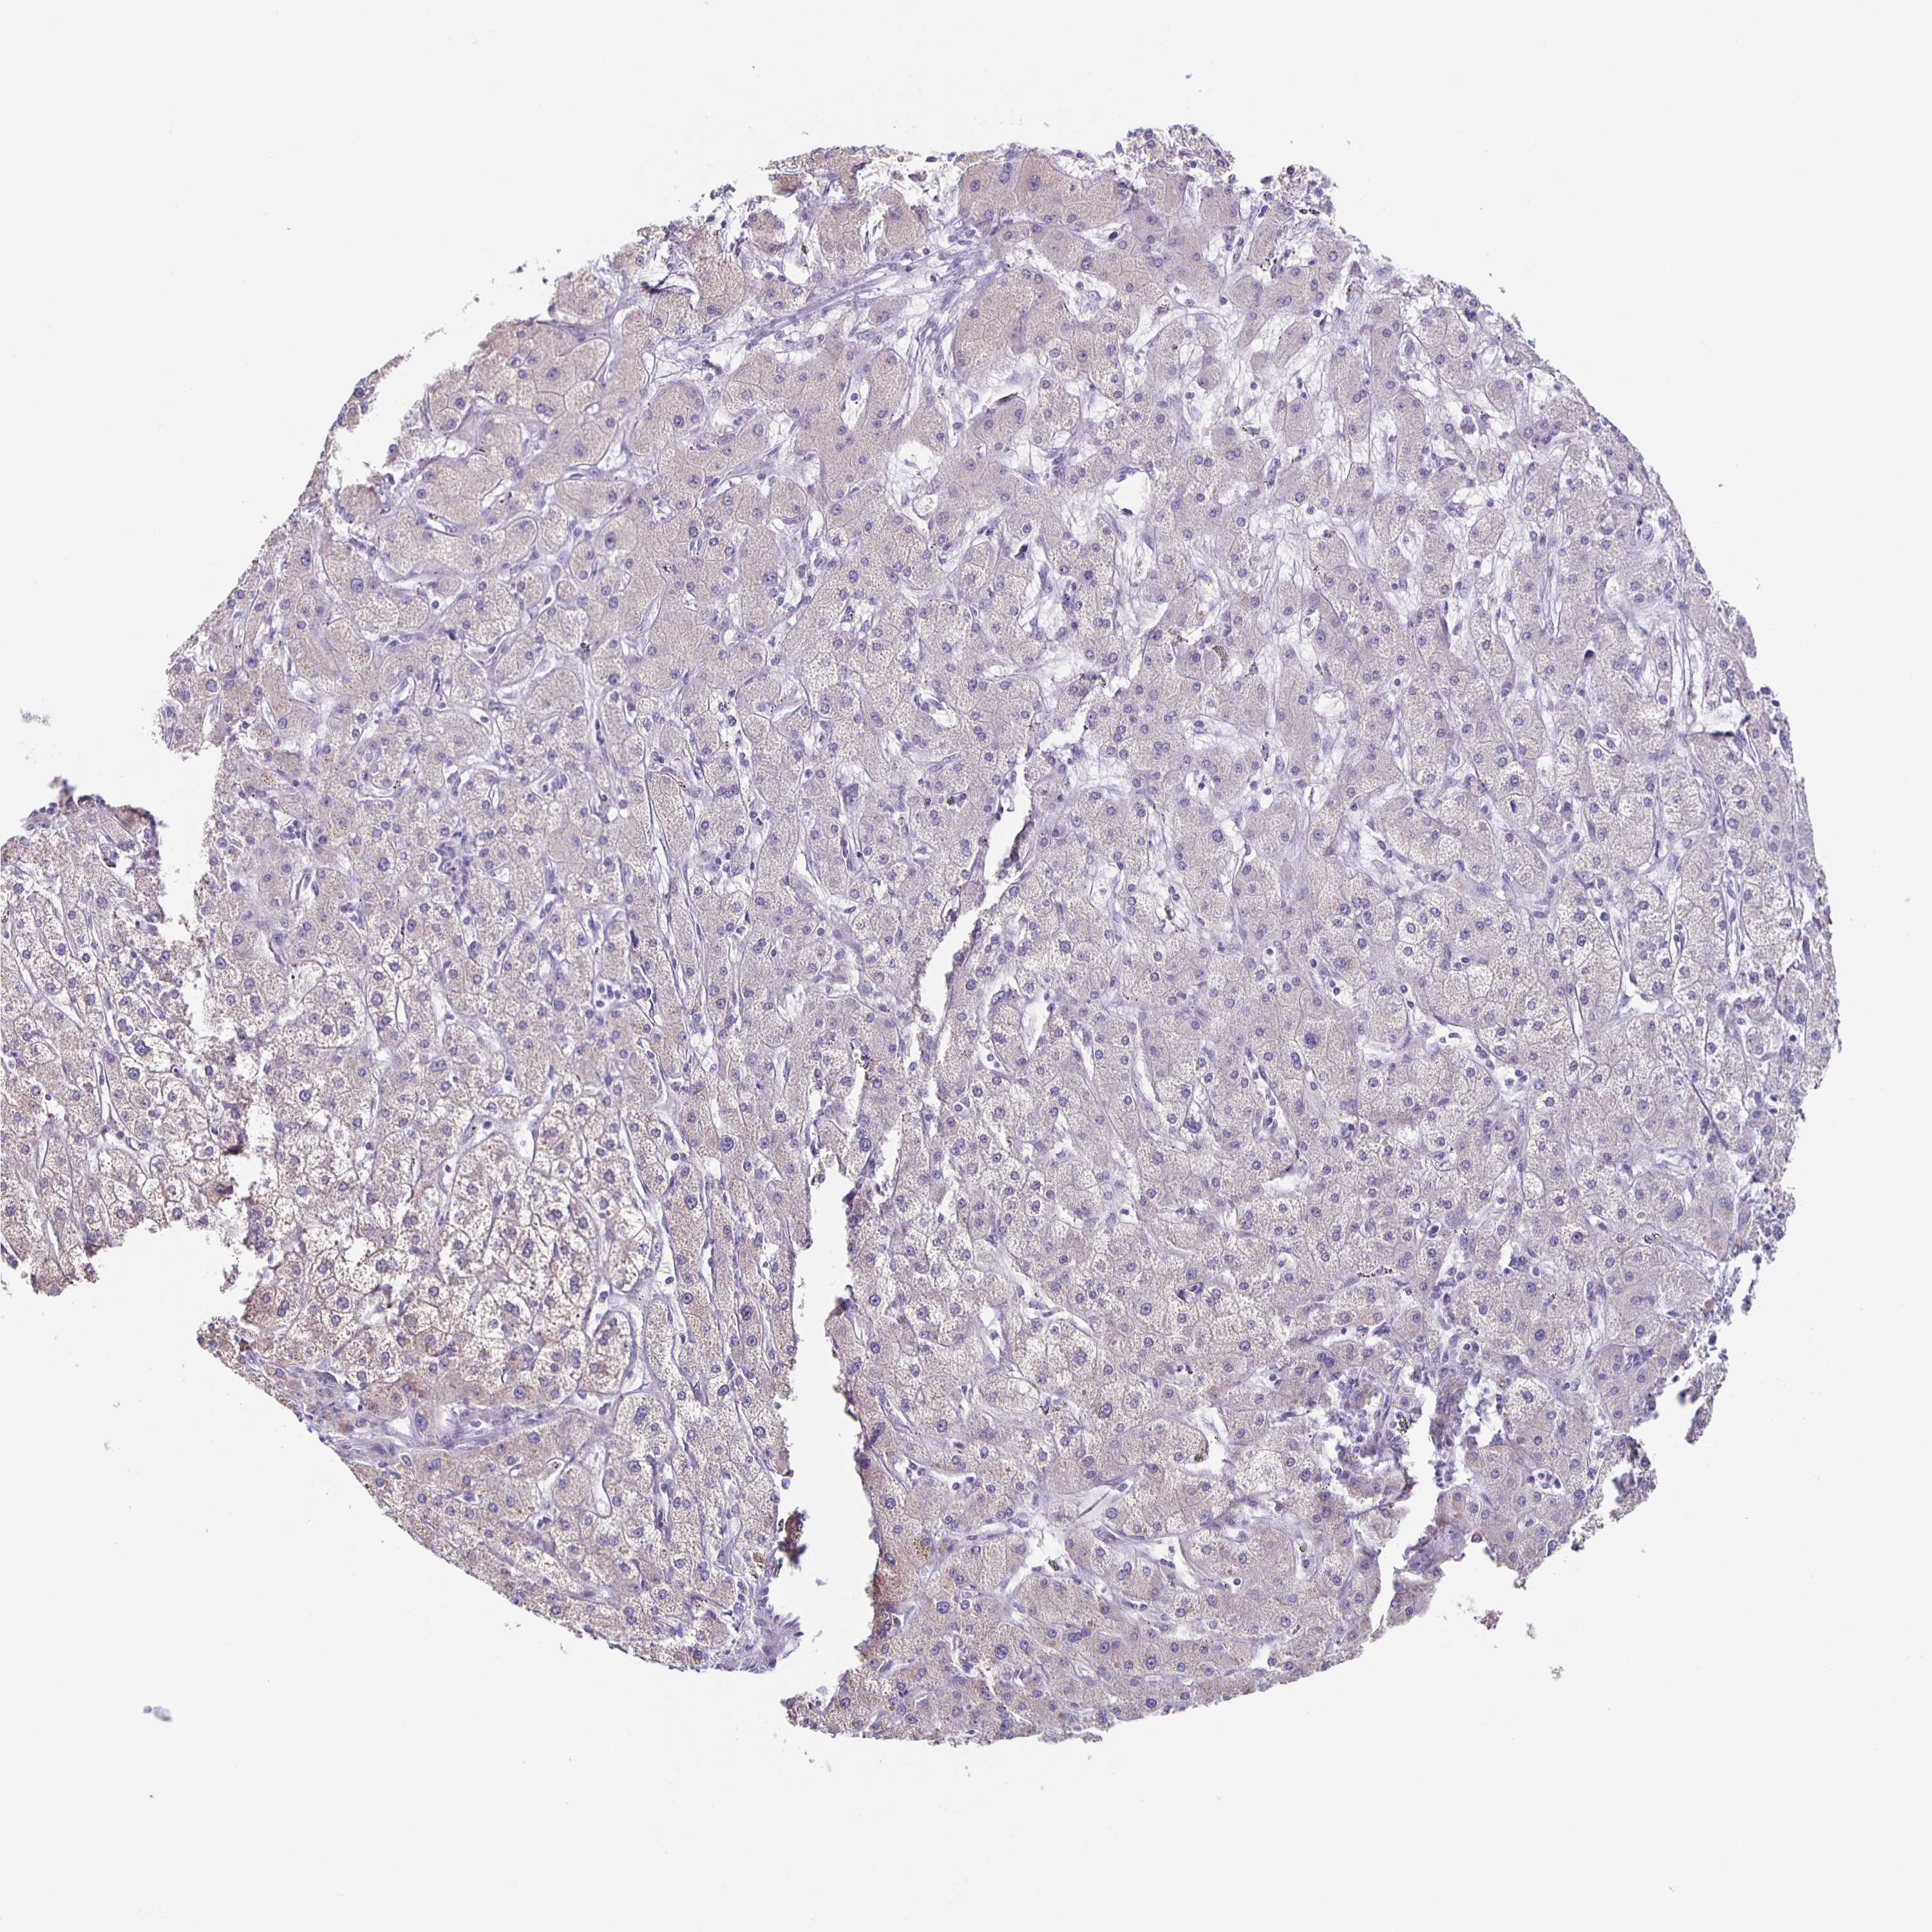

LIVER CANCER - Protein expressioni

A mouse-over function shows sample information and annotation data. Click on an image to view it in a full screen mode. Samples can be filtered based on level of antibody staining by selecting one or several of the following categories: high, medium, low and not detected. The assay and annotation is described here.

Antibody stainingi

Antibody staining in the annotated cell types in the current human tissue is reported as not detected, low, medium, or high, based on conventional immunohistochemistry profiling in selected tissues. This score is based on the combination of the staining intensity and fraction of stained cells.

Each image is clickable and will lead to virtual microscopy that enables deeper exploration of all samples and also displays staining intensity scores, fraction scores and subcellular localization as well as patient and tissue information for each sample.

Antibody HPA036575

Antibody HPA036576

Carcinoma, Hepatocellular, NOS

Cholangiocarcinoma